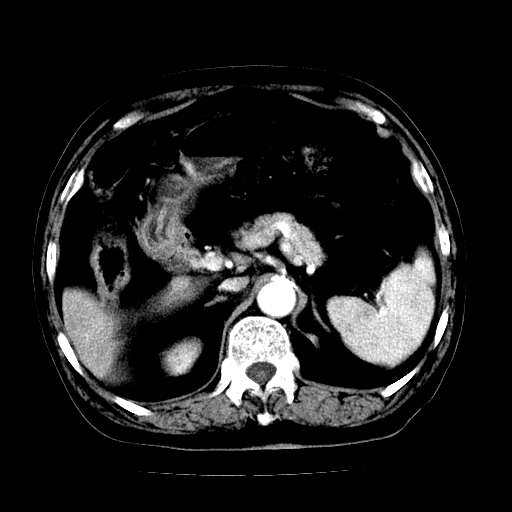

男,71岁,皮肤黄染四天。

肝内外胆管及胆总管上段扩张,考虑为梗阻所致,建议mrcp检查。

考虑胆总管癌并肝内外胆管扩张。

胆管癌并肝内外胆管扩张。

支持考虑胆总管癌并肝内外胆管扩张。 局部应薄扫。心包钙化。

胰腺上端胆总管内见软组织影,强化不明显,结合临床,还是考虑低位梗阻性黄疸,胆总管癌可能性大